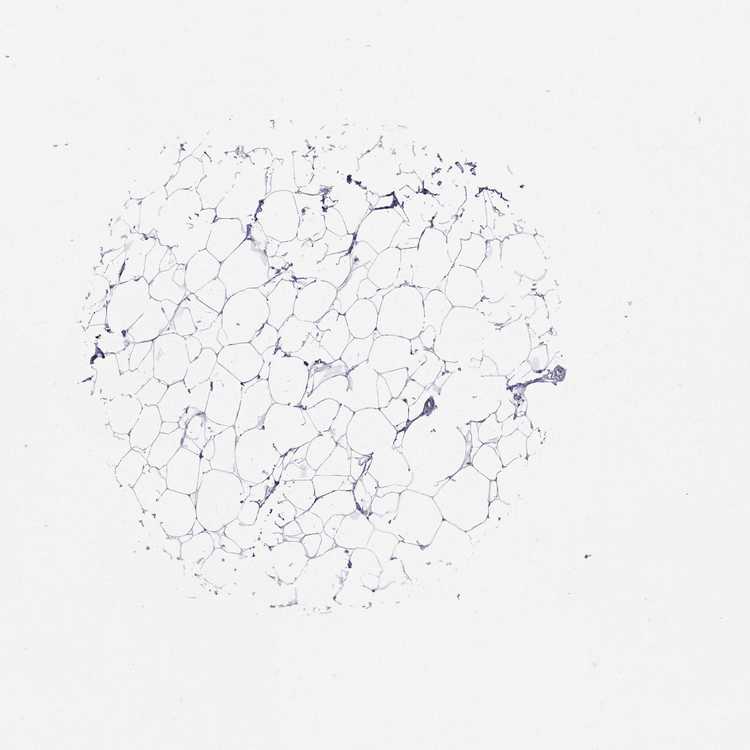

BREAST - Antibody stainingi

Antibody staining in the annotated cell types in the current human tissue is reported as not detected, low, medium, or high, based on conventional immunohistochemistry profiling in selected tissues. This score is based on the combination of the staining intensity and fraction of stained cells.

Each image is clickable and will lead to virtual microscopy that enables deeper exploration of all samples and also displays staining intensity scores, fraction scores and subcellular localization as well as patient and tissue information for each sample.

Antibody HPA065600Antibody CAB055172Antibody CAB080360

Adipocytes Not detectedNot detectedNot detected

Glandular cells Not detectedMediumNot detected

Myoepithelial cells Not detectedNot detectedNot detected